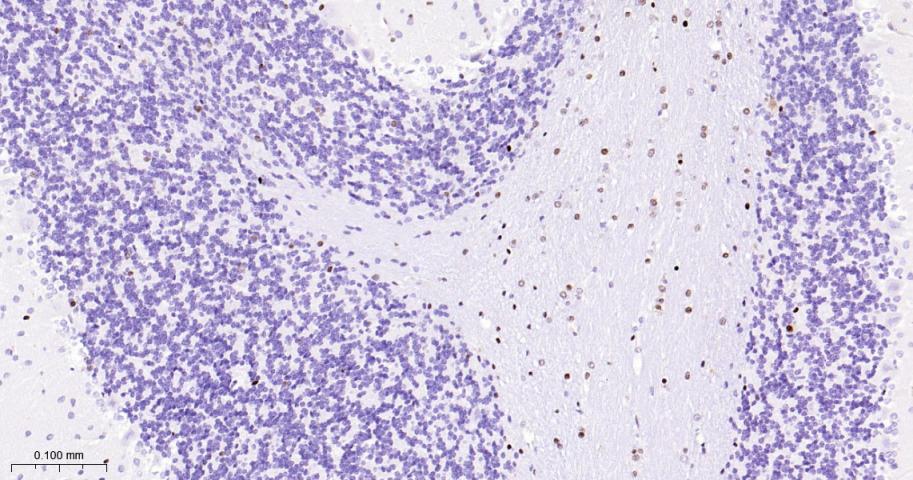

Paraformaldehyde-fixed, paraffin embedded Mouse Cerebellum; Antigen retrieval by boiling in sodium citrate buffer (pH6.0) for 15 min; The section was incubated with OLIG2 Monoclonal Antibody, Unconjugated (bsm-61115R) at 1:200 overnight at 4°C, followed by conjugation to the bs-0295G-HRP and DAB (C-0010) staining.

Paraformaldehyde-fixed, paraffin embedded Human Glioma; Antigen retrieval by boiling in sodium citrate buffer (pH6.0) for 15 min; Antibody incubation with OLIG2 Monoclonal Antibody, Unconjugated(bsm-61115R) at 1:200 overnight at 4°C, followed by conjugation to the bs-0295G-HRP and DAB (C-0010) staining.

Paraformaldehyde-fixed, paraffin embedded Rat Cerebellum; Antigen retrieval by boiling in sodium citrate buffer (pH6.0) for 15 min; Antibody incubation with OLIG2 Monoclonal Antibody, Unconjugated(bsm-61115R) at 1:200 overnight at 4°C, followed by conjugation to the bs-0295G-HRP and DAB (C-0010) staining.

Paraformaldehyde-fixed, paraffin embedded Human Cerebrum; Antigen retrieval by boiling in sodium citrate buffer (pH6.0) for 15 min; Antibody incubation with OLIG2 Monoclonal Antibody, Unconjugated(bsm-61115R) at 1:200 overnight at 4°C, followed by conjugation to the bs-0295G-HRP and DAB (C-0010) staining.

Paraformaldehyde-fixed, paraffin embedded Rat Cerebrum; Antigen retrieval by boiling in sodium citrate buffer (pH6.0) for 15 min; Antibody incubation with OLIG2 Monoclonal Antibody, Unconjugated(bsm-61115R) at 1:200 overnight at 4°C, followed by conjugation to the bs-0295G-HRP and DAB (C-0010) staining.

Paraformaldehyde-fixed, paraffin embedded Mouse Cerebrum; Antigen retrieval by boiling in sodium citrate buffer (pH6.0) for 15 min; Antibody incubation with OLIG2 Monoclonal Antibody, Unconjugated(bsm-61115R) at 1:200 overnight at 4°C, followed by conjugation to the bs-0295G-HRP and DAB (C-0010) staining.